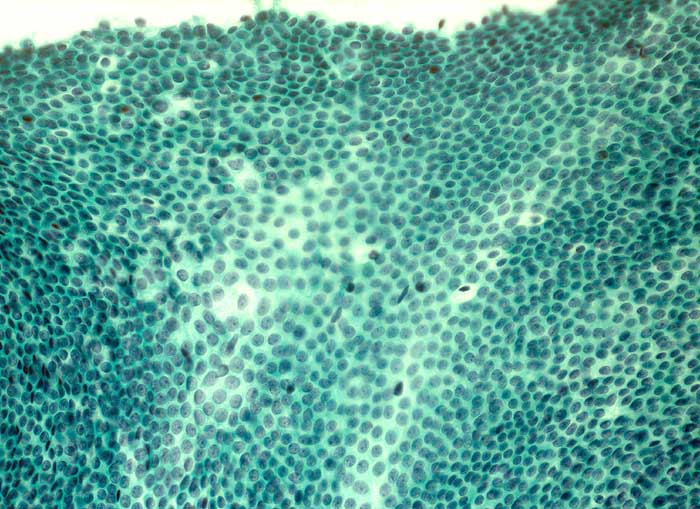

Grosse Mengen epithelialer Zellen, bipolarer Nacktkerne (Myofibroblasten und Fibrozyten) und scharf begrenzte Stromafragmente charakterisieren das Fibroadenom zytologisch. Aspirate von stark fibrosierten Fibroadenomen können auch zellarm sein. Einseitig von Epithel bedeckte Bindegewebsfragmente sprechen für ein Fibroadenom. Durch die Aspiration wird die epitheliale Innenauskleidung mit ihren Verzweigungen aus dem Gangsystem gelöst. Die Epithelverbände sind beim intrakanalikulären Fibroadenom flach und erscheinen beim perikanalikulären Fibroadenom T-, Y-, finger- oder hirschgeweihförmig. Die Kerne sind wenig grösser als die Kerne normaler duktaler Epithelien und messen meist weniger als zwei Erythrozytendurchmesser. Da es sich bei Fibroadenomen um proliferierende Läsionen handelt können die Epithelzellen Zeichen der Aktivierung zeigen in Form einer mässig ausgeprägten Pleomorphie, prominenten Nukleolen, und gelegentlichen Mitosen.

Das erste Beispiel zeigt ein intrakanalikuläres, das zweite Beispiel ein perikanalikuläres Fibroadenom mit stark verzweigten Zellverbänden. Das dritte Beispiel zeigt die Zytomorphologie eines Fibroadenoms mit stark aktivierten Zellen.